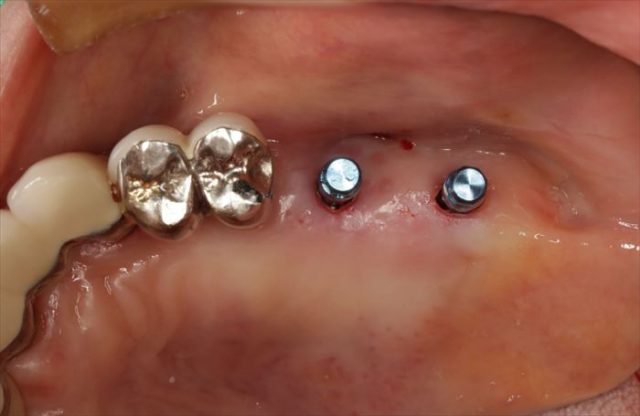

インプラント埋入を終えました。

頬側面観です。

青いパーツはインプラント埋入用の挿入ジグです。

挿入ジグを外しました。